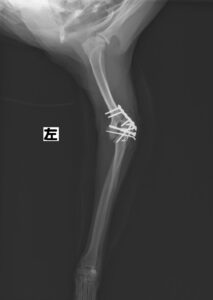

階段からころげおちてかかりつけ医を受診し、X線にて左側「上腕骨外顆骨折」を認めたため、当院の整形外科にご紹介いただきました。この症例は、尺骨の骨切り術を併用し外顆の骨折部分を整復しています。術後の経過は良好で、手術から7ヶ月後に尺骨のインプラントを除去し、治療終了としました。